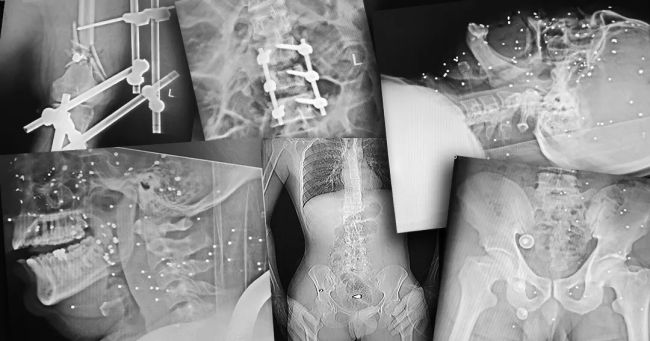

شلیک به اندامهای حیاتی

تصاویر رادیوگرافی و سیتیاسکن نشان میدهد اندام حیاتی تعداد زیادی از معترضان هدف شلیک ماموران امنیتی و نظامی قرار گرفته است. گردن، قفسه سینه، شکم، ستون فقرات و ناحیه تناسلی نقاطی هستند که به کرات هدف تیرهای ساچمهای و گاهی جنگی قرار گرفتهاند. همچنین تعداد زیادی از معترضان تنها از یک ناحیه هدف قرار نگرفتهاند؛ در یکی از موارد تیرهای ساچمهای در سر، گردن، کتف، قفسه سینه، پهلو و لگن فرد بستری دیده میشود. این موارد میتواند حاصل شلیک بیش از یک بار به سمت این معترض باشد. کیانا کثیری در این مورد میگوید که برخی آسیبهای واردشده به این معترض «دائمی» است و تا پایان عمر همراه او خواهد بود.

برخی از معترضان نیز با گلوله جنگی و به شکل مشخص از ناحیه اندام حیاتی هدف قرار گرفتهاند. در یکی از تصاویر رادیوگرافی گلوله یا ترکش در قفسه سینه و در ناحیه ریه مجروح دیده میشود، در تصویری دیگر گلوله جنگی در ناحیه تناسلی یک مرد قرار دارد و در موردی دیگر گلوله در نزدیکی ستون فقرات بیمار ثابت مانده است. کیانا کثیری در مورد عکس آخر میگوید: «در این عکس دو نوع آسیب را مشاهده میکنیم. یکی اصابت ناحیه پشت با گلوله جنگی، بر اساس ورود و قرار گرفتن گلوله به نظر میرسد که گلوله از بالا شلیک شده و آسیب دوم شکستگی سه مهره کمری،Lumbal Columna است که نیاز به ترمیم با فیکسیشنهای ارتوپدی داشته است.»

دست و پای معترضان در شهر رشت نیز از شلیکهای ماموران جمهوری اسلامی در امان نبودهاند. تصاویر رادیوگرافی نشان میدهد بسیاری از معترضان در ناحیه دست و پا هدف تیرهای ساچمهای قرار گرفتهاند، شدت آسیب در برخی موارد تا حدی بوده که استخوان ساعد، ساق یا مچ پا خرد شدهاند. همچنین موارد متعددی از شکستگی در دست و پای معترضان بدون شلیک گلوله نیز دیده میشود.

یکی از شدیدترین جراحات متعلق به زنی است که نه تنها کتف، بازو، ران و ناحیه تناسلی او هدف تیر ساچمهای قرار گرفته است، بلکه استخوان ران او نیز با اصابت گلوله جنگی خرد شده است. در تصاویر مشخص است که از فیکساتور برای درمان این مجروح استفاده شده است.

استخوانهای خردشده دست و پادست و پای معترضان در شهر رشت نیز از شلیکهای ماموران جمهوری اسلامی در امان نبودهاند. تصاویر رادیوگرافی نشان میدهد بسیاری از معترضان در ناحیه دست و پا هدف تیرهای ساچمهای قرار گرفتهاند، شدت آسیب در برخی موارد تا حدی بوده که استخوان ساعد، ساق یا مچ پا خرد شدهاند. همچنین موارد متعددی از شکستگی در دست و پای معترضان بدون شلیک گلوله نیز دیده میشود.